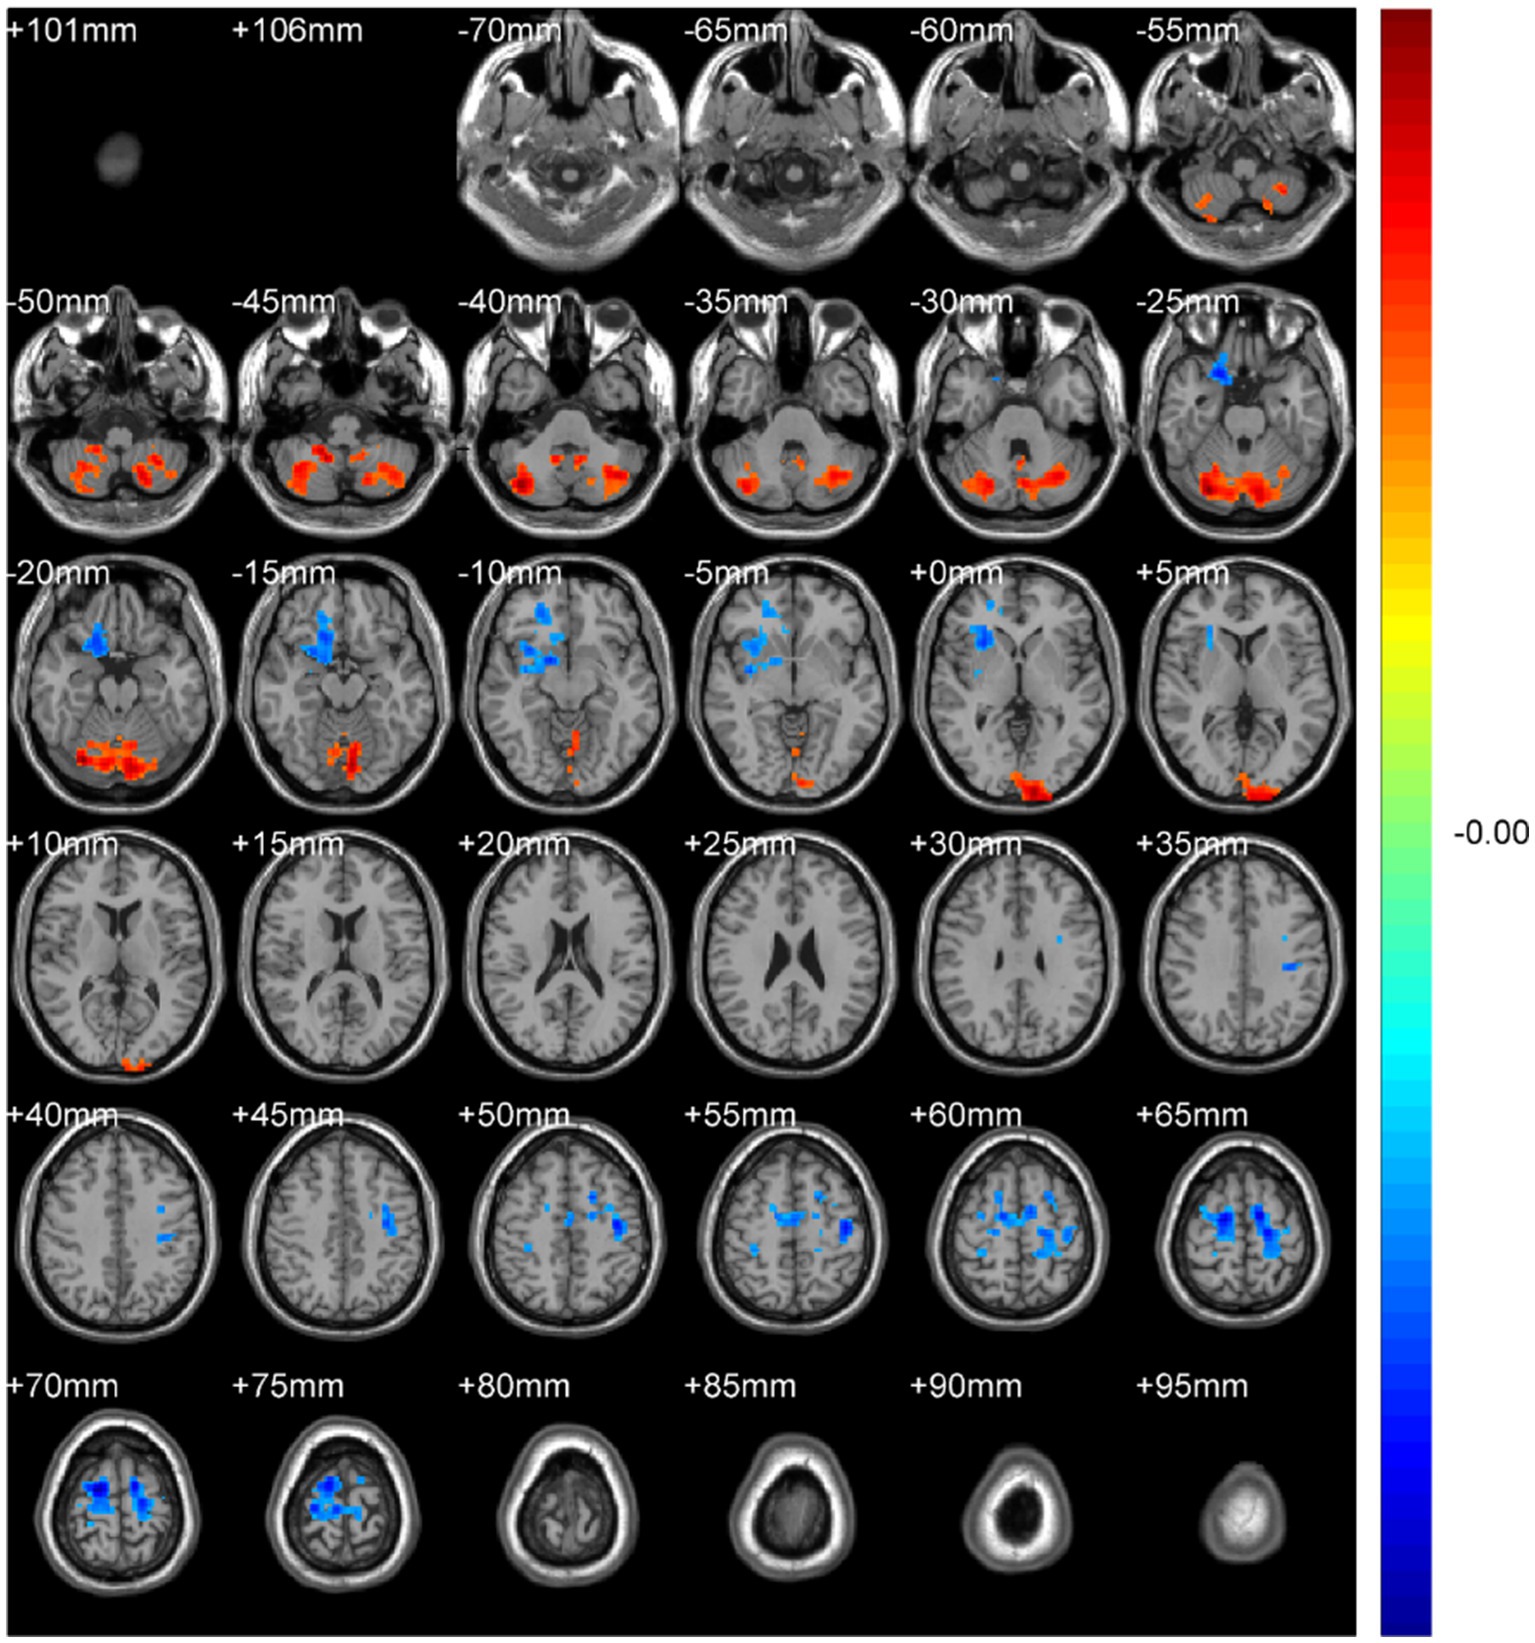

ABSTRACT Background: Spinal diseases related pain represents a critical clinical issue that demands urgent resolution. Current treatment and assessment strategies predominantly focus on peripheral mechanisms. The application of functional magnetic resonance imaging (fMRI) offers a promising approach to identifying potential central targets for intervention. Methods: We retrospectively included 31 patients with spinal diseases related pain and 32 controls with non-spinal, orthopedic complaints (no chronic neurological or psychiatric disorders). All participants underwent resting-state brain fMRI (eyes closed, awake). We quantified amplitude of low-frequency fluctuations (ALFF) with mean normalization (mALFF) and z-transformation (zALFF), regional homogeneity (ReHo; 27-voxel neighborhood), seed-based functional connectivity (FC; pre/postcentral seeds), and degree centrality (DC; binary and weighted). Between group tests used voxel-wise two-sample t_tests with Gaussian Random Field (GRF) correction. Results: Patient group was associated with increased m/zALFF in right cerebellar lobule IX and right Superior Frontal Gyrus, medial part , and lower activity in bilateral postcentral gyri and the Cuneus. , decreased m/zALFF in bilateral postcentral gyri. ReHo analysis confirmed reduced local synchrony in postcentral regions , spatially overlapping with ALFF findings. FC analyses revealed enhanced cerebellar-thalamic connectivity (Crus1/2, thalamus) but reduced connectivity in sensorimotor and higher-order cortical networks. DC showed hyperconnectivity in left cerebellar Crus I with reduced Superior Frontal Orbital (Frontal_Sup_Orb). All findings survived GRF correction at the pre_specified thresholds. Conclusions: Resting-state brain fMRI indicates a cerebello-thalamo-cortical alteration pattern in spinal diseases related pain featuring cerebellar involvement, prefrontal subspecialization, and multilevel sensorimotor disruption. These cross-sectional associations may inform hypothesis-generation for future neuromodulation studies and provide candidate biomarkers for monitoring, pending prospective validation.